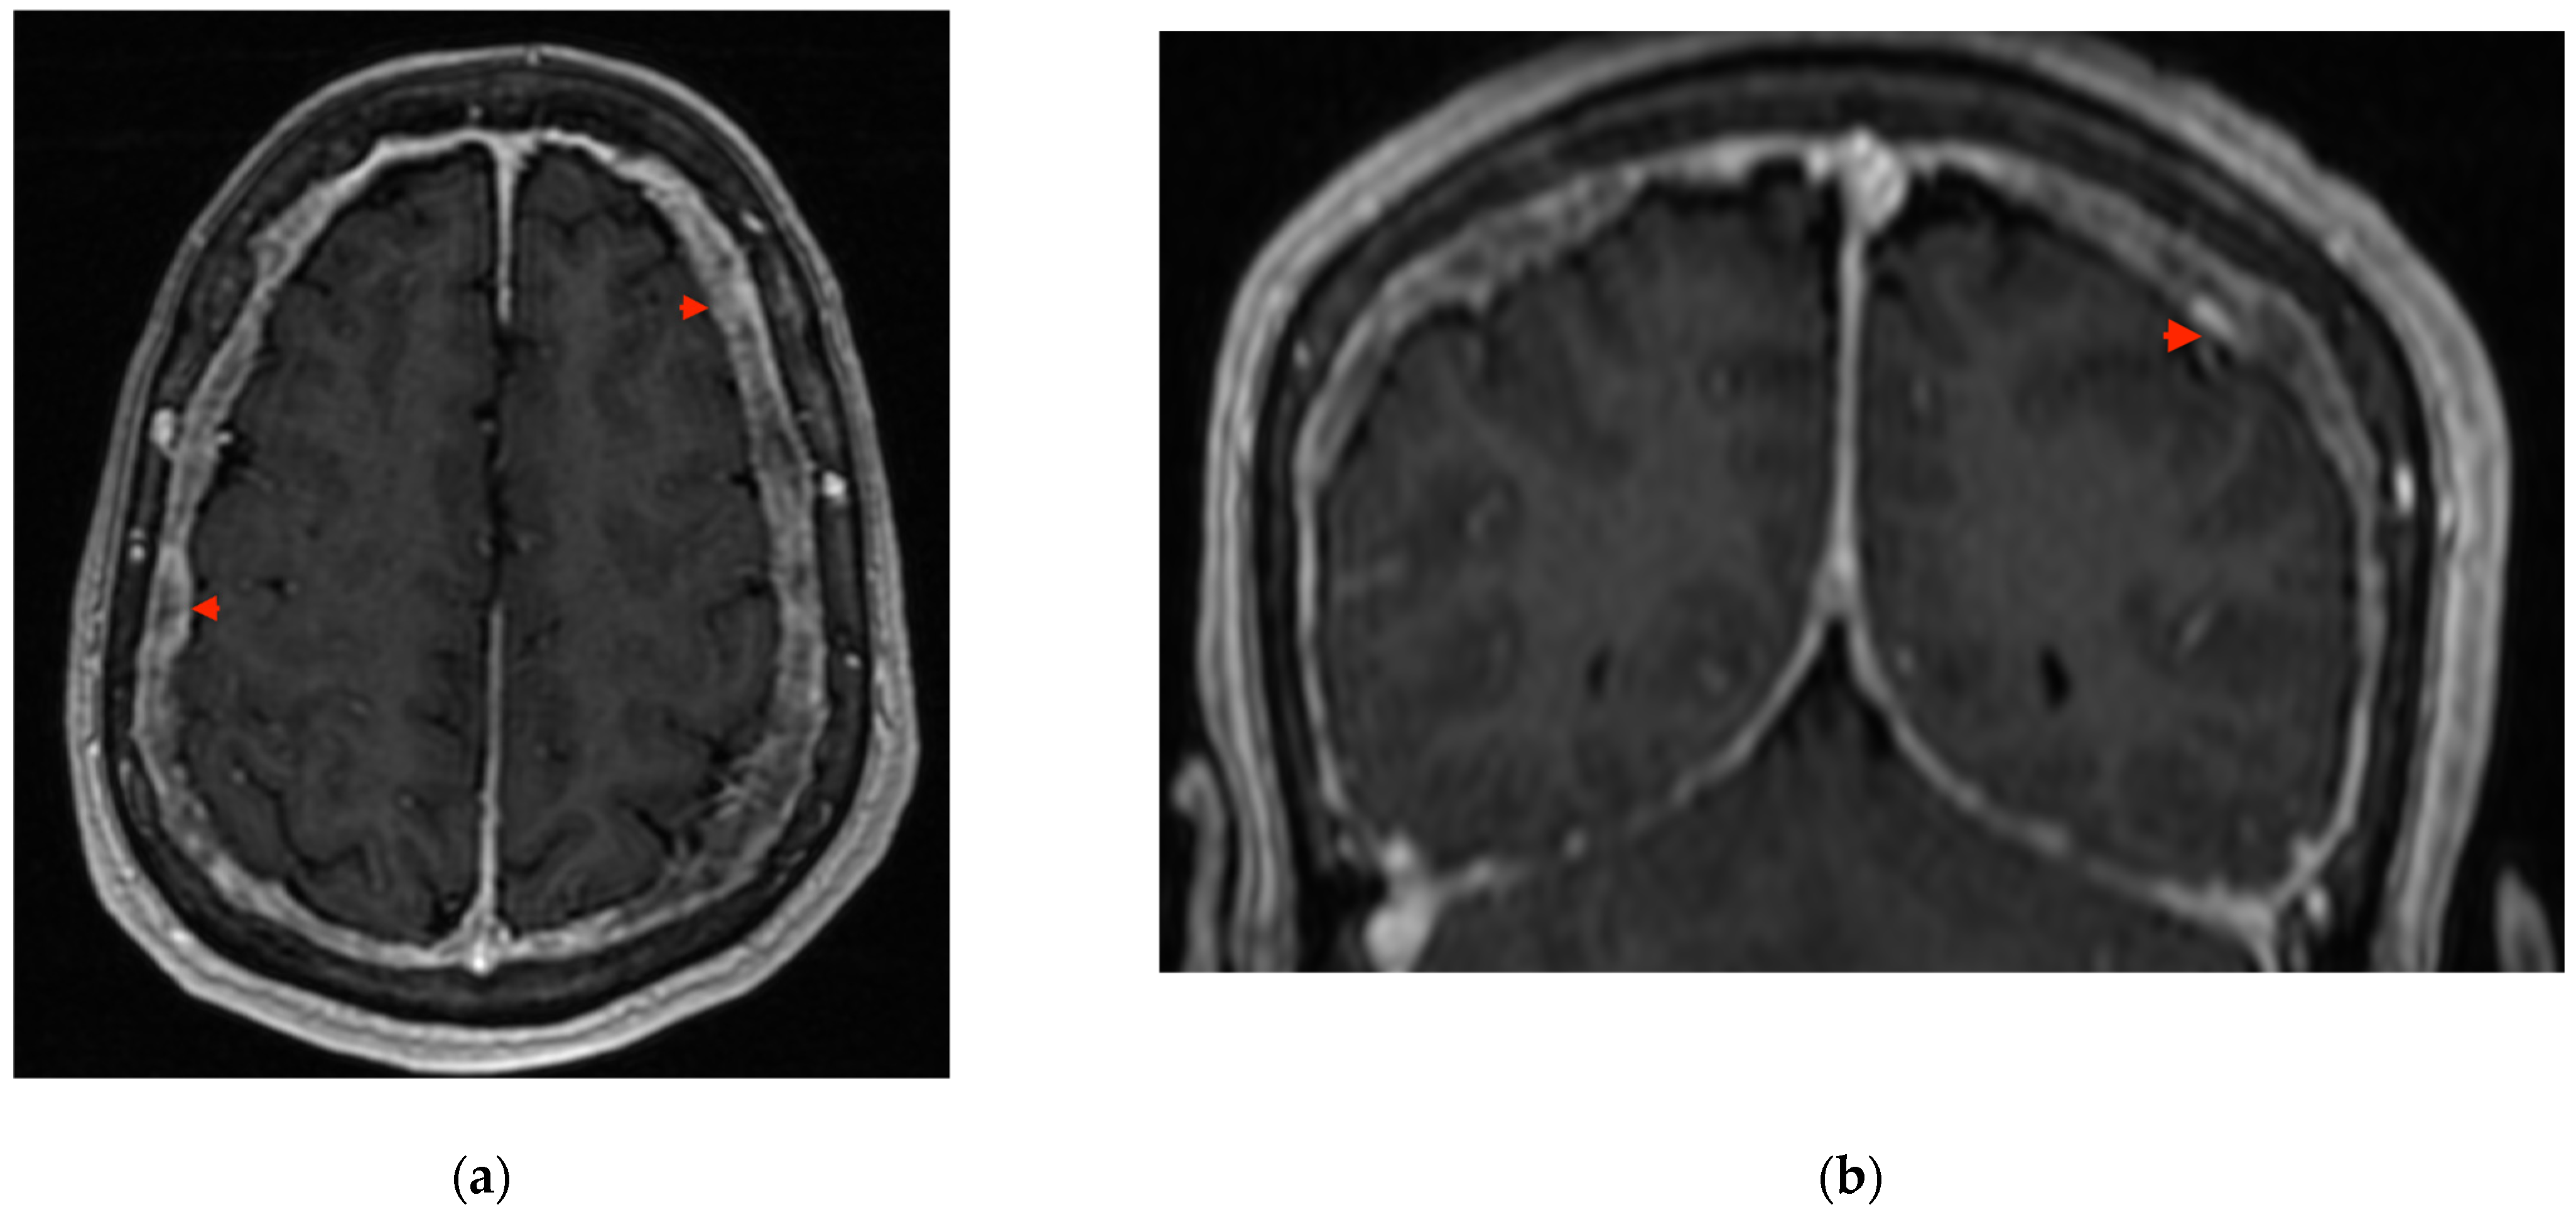

2. Case Presentation